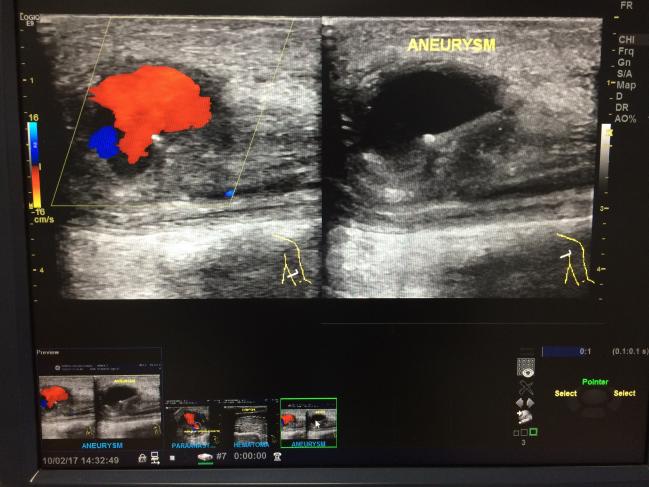

Travel with confidence and purchase foreign currency in advance through AAA More than 80 currencies are available for purchase either online or at your local AAA and delivered nextday Reloadable prepaid card offers travelers a safe and convenient alternative to cash and worldwide Visa acceptance, plus ATM accessAAA Innovations offers better, more imaginative, and higher quality goods at all price points Our goal is to offer unique, exclusive, technologically superior products that your clients agree have greater value Our passion is to make sure your experience with AAA is the best it can be, every time, from 1909 through today The aorta carries blood from your heart to your abdomen, legs, and pelvis When the abdominal aortic walls are swollen, it's known as abdominal aortic aneurysm

Please check your number and try again, or enter your 16digit membership number as displayed on your card It looks like your membership number does not belong to AAA Carolinas If you've reached AAA Carolinas by accident, you can find your club by returning to AAAcom If you need assistance logging in, call us atYou get bestinclass 24/7 roadside assistance, towing, insurance, discounts, and more Enjoy peace of mind Join AAA today!Once a AAA has reached 56 centimeters in diameter, about the size of an orange, the risk of rupture is very substantial, probably about 50/50 over the next few years Most vascular surgeons would agree that a 56 cm aneurysm should be repaired, unless other medical factors in a patient make the operation too risky

An AAA is typically defined as aortic enlargement with a diameter of 30 cm or larger The prevalence of AAA has declined over the past 2 decades among screened men 65 years or older in various countries such as the United Kingdom, New Zealand, Sweden, and Denmark 110 Populationbased studies in men older than 60 years have found an AAA prevalence rangingAbdominal aortic aneurysm (AAA) screening is a way of checking if there's a bulge or swelling in the aorta, the main blood vessel that runs from your heart down through your tummy This bulge or swelling is called an abdominal aortic aneurysm, or AAAProtect your loved ones with help from AAA Life Insurance We offer a variety of life insurance solutions, including Term, Whole, and Universal Life Insurance

AAA Members can save on insurance, travel and much more See how membership can pay for itself with hundreds of services and discounts Serving residents and AAA Members in Florida, Georgia, Illinois, Indiana, Iowa, Michigan, Minnesota, Nebraska, North Dakota, Tennessee, Wisconsin and Puerto RicoBy selecting "Continue", you will leave cardcreditcardacgaaacom and enter a third party Web site cardcreditcardacgaaacom is not responsible for the content of, or products and services provided by , nor does it guarantee the system availability or accuracy of information contained in the siteThis Web site is not controlled by cardcreditcardacgaaacomRupture is most likely to occur on the left posterolateral wall 2 to 4 cm below the renal arteries If an AAA ruptures, most patients die before reaching a medical facility Patients who do not die immediately typically present with abdominal or back pain, hypotension, and tachycardia

New Mexico AAA Albuquerque East Montgomery Blvd NE, Albuquerque, NM September 1317 9 am to noon, 1 to 5 pm Pennsylvania AAA Bethlehem 15 Stefko Blvd, Bethlehem, PA August 2327 9 am to noon, 1 to 5 pm Texas AAA Flower Mound 60 Long Prairie Rd #0, Flower Mound, TX AAA 7 cm 33% annual risk of AAA rupture (50% lifetime risk of rupture) Course of small aortic aneurysms (American Airlines has airline tickets, cheap flights, vacation packages and American Airlines AAdvantage bonus mile offers at aacom

With an AAA of 40 to 49 cm in diameter 2 C We suggest surveillance imaging at 6 month intervals for patients with an AAA between 50 and 54 cm in diameter 2 C We recommend a CT scan to evaluate patients thought to have AAA presenting with recent onset abdominal or back pain, particularly in the presence of a pulsatile epigastric mass or